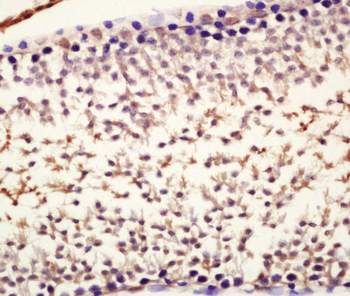

应用稀释比例:WB=1:500-2000, IHC-P=1:100-500, IHC-F=1:100-500, IF=1:100-500